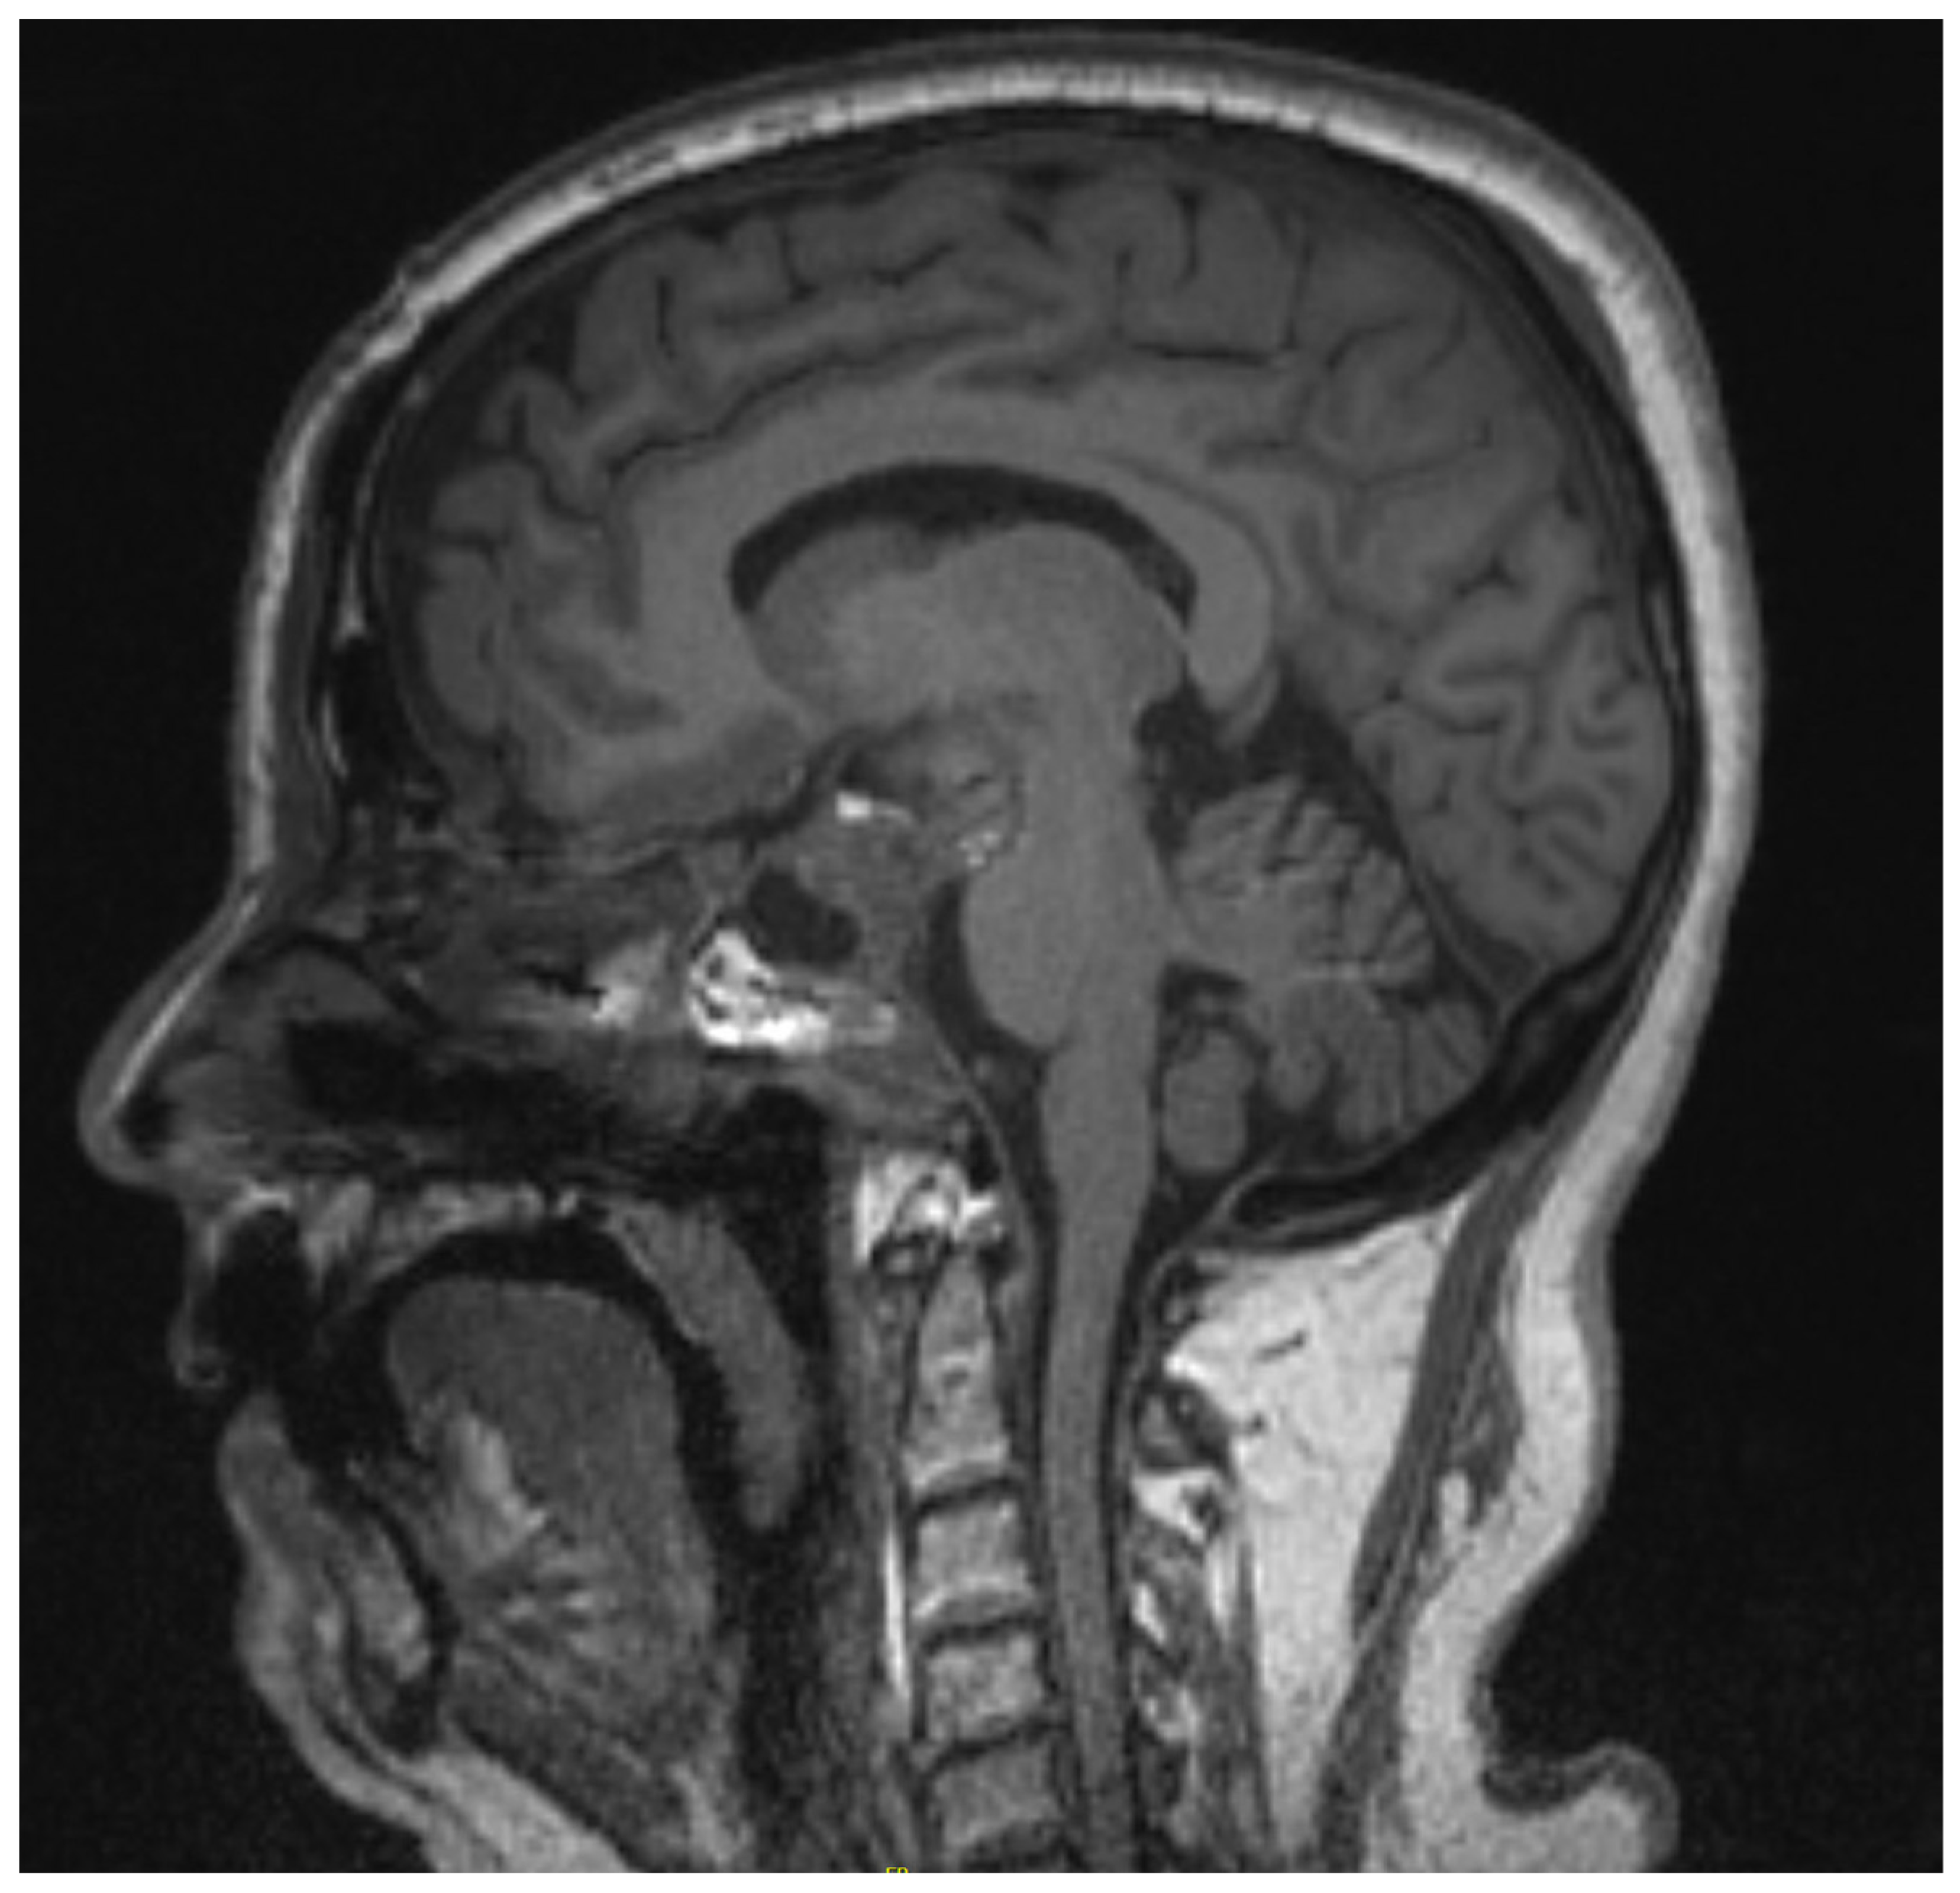

2.1. Case 1

2.2. Case 2